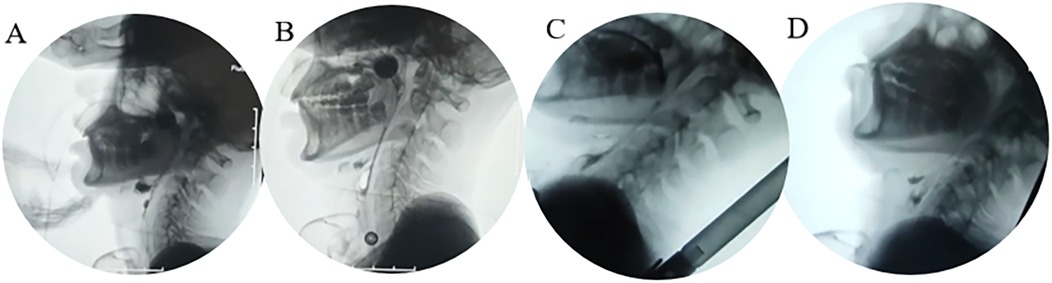

Background: Dysphagia is a common complication of severe traumatic brain injury (sTBI) and may persist despite standard treatment. For refractory cases, there appear to be no more effective therapeutic options available. Case information: A 15-year-old boy continued to suffer from severe dysphagia nine months after severe traumatic brain injury, remaining dependent on tracheostomy and nasogastric feeding. Prior interventions, including two botulinum toxin injections and a 35-day multimodal rehabilitation program, failed to yield meaningful improvement. At readmission, swallowing assessments showed profound impairment, malnutrition, and poor treatment tolerance. Functional near-infrared spectroscopy (fNIRS) was then applied to map cortical activation and guide targeted therapy. After 42 days, swallowing function improved significantly, with the Functional Oral Intake Scale (FOIS) rising from level I to VI and the Penetration-Aspiration Scale (PAS) decreasing from 8 to 2. Conclusions: The therapeutic outcome of this case suggests that selecting training methods based on fNIRS-identified cortical activation can have a positive and significant impact on swallowing rehabilitation in patients with severe traumatic brain injury.